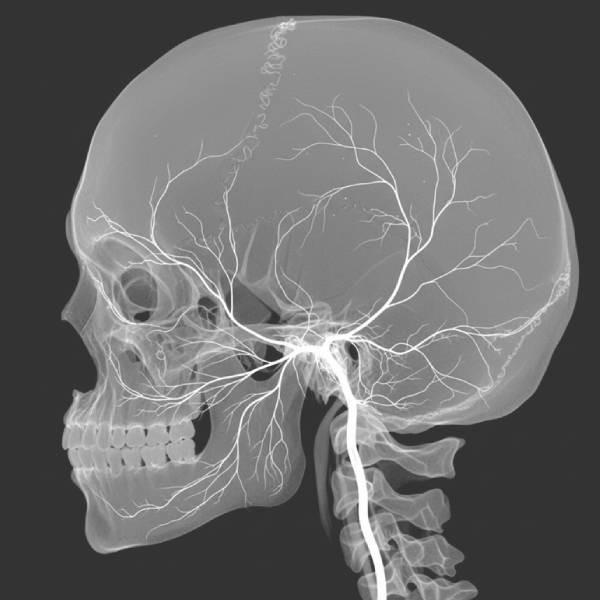

धमनीशिरापरक फिस्टुला का निदान कैसे किया जाता है

निदान कभी भी अनुमान पर आधारित नहीं होता है। उसमे समाविष्ट हैं:

- लक्षित इमेजिंग परीक्षण जैसे:

- डॉपलर अल्ट्रासाउंड

- सीटी एंजियोग्राफी

- एमआरआई या एमआर एंजियोग्राफी

प्रत्येक रिपोर्ट को चरण-दर-चरण समझाया जाता है ताकि रोगी चुनने से पहले अपनी स्थिति को पूरी तरह से समझ सकें नारनौल में एवीएफ उपचार .